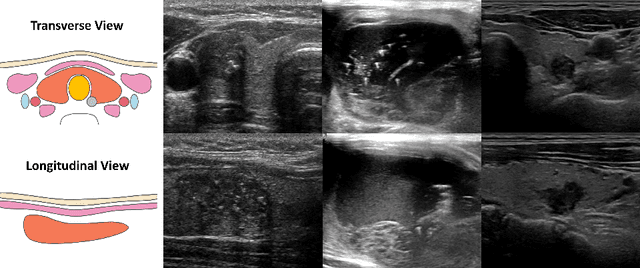

Abstract:Thyroid nodule classification and segmentation in ultrasound images are crucial for computer-aided diagnosis; however, they face limitations owing to insufficient labeled data. In this study, we proposed a multi-view contrastive self-supervised method to improve thyroid nodule classification and segmentation performance with limited manual labels. Our method aligns the transverse and longitudinal views of the same nodule, thereby enabling the model to focus more on the nodule area. We designed an adaptive loss function that eliminates the limitations of the paired data. Additionally, we adopted a two-stage pre-training to exploit the pre-training on ImageNet and thyroid ultrasound images. Extensive experiments were conducted on a large-scale dataset collected from multiple centers. The results showed that the proposed method significantly improves nodule classification and segmentation performance with limited manual labels and outperforms state-of-the-art self-supervised methods. The two-stage pre-training also significantly exceeded ImageNet pre-training.

Abstract:Over the past decades, the incidence of thyroid cancer has been increasing globally. Accurate and early diagnosis allows timely treatment and helps to avoid over-diagnosis. Clinically, a nodule is commonly evaluated from both transverse and longitudinal views using thyroid ultrasound. However, the appearance of the thyroid gland and lesions can vary dramatically across individuals. Identifying key diagnostic information from both views requires specialized expertise. Furthermore, finding an optimal way to integrate multi-view information also relies on the experience of clinicians and adds further difficulty to accurate diagnosis. To address these, we propose a personalized diagnostic tool that can customize its decision-making process for different patients. It consists of a multi-view classification module for feature extraction and a personalized weighting allocation network that generates optimal weighting for different views. It is also equipped with a self-supervised view-aware contrastive loss to further improve the model robustness towards different patient groups. Experimental results show that the proposed framework can better utilize multi-view information and outperform the competing methods.